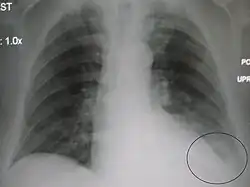

| A chest X-ray showing a very prominent wedge-shape bacterial pneumonia in the right lung | |

AP CXR showing left lower lobe pneumonia associated with a small left sided pleural effusion -

AP CXR showing right lower lobe pneumonia -

AP CXR showing pneumonia of the lingula of the left lung -

Right upper lobe pneumonia as marked by the circle. -

Left upper lobe pneumonia with a small pleural effusion.

Right lower lobe pneumonia as seen on a lateral CXR